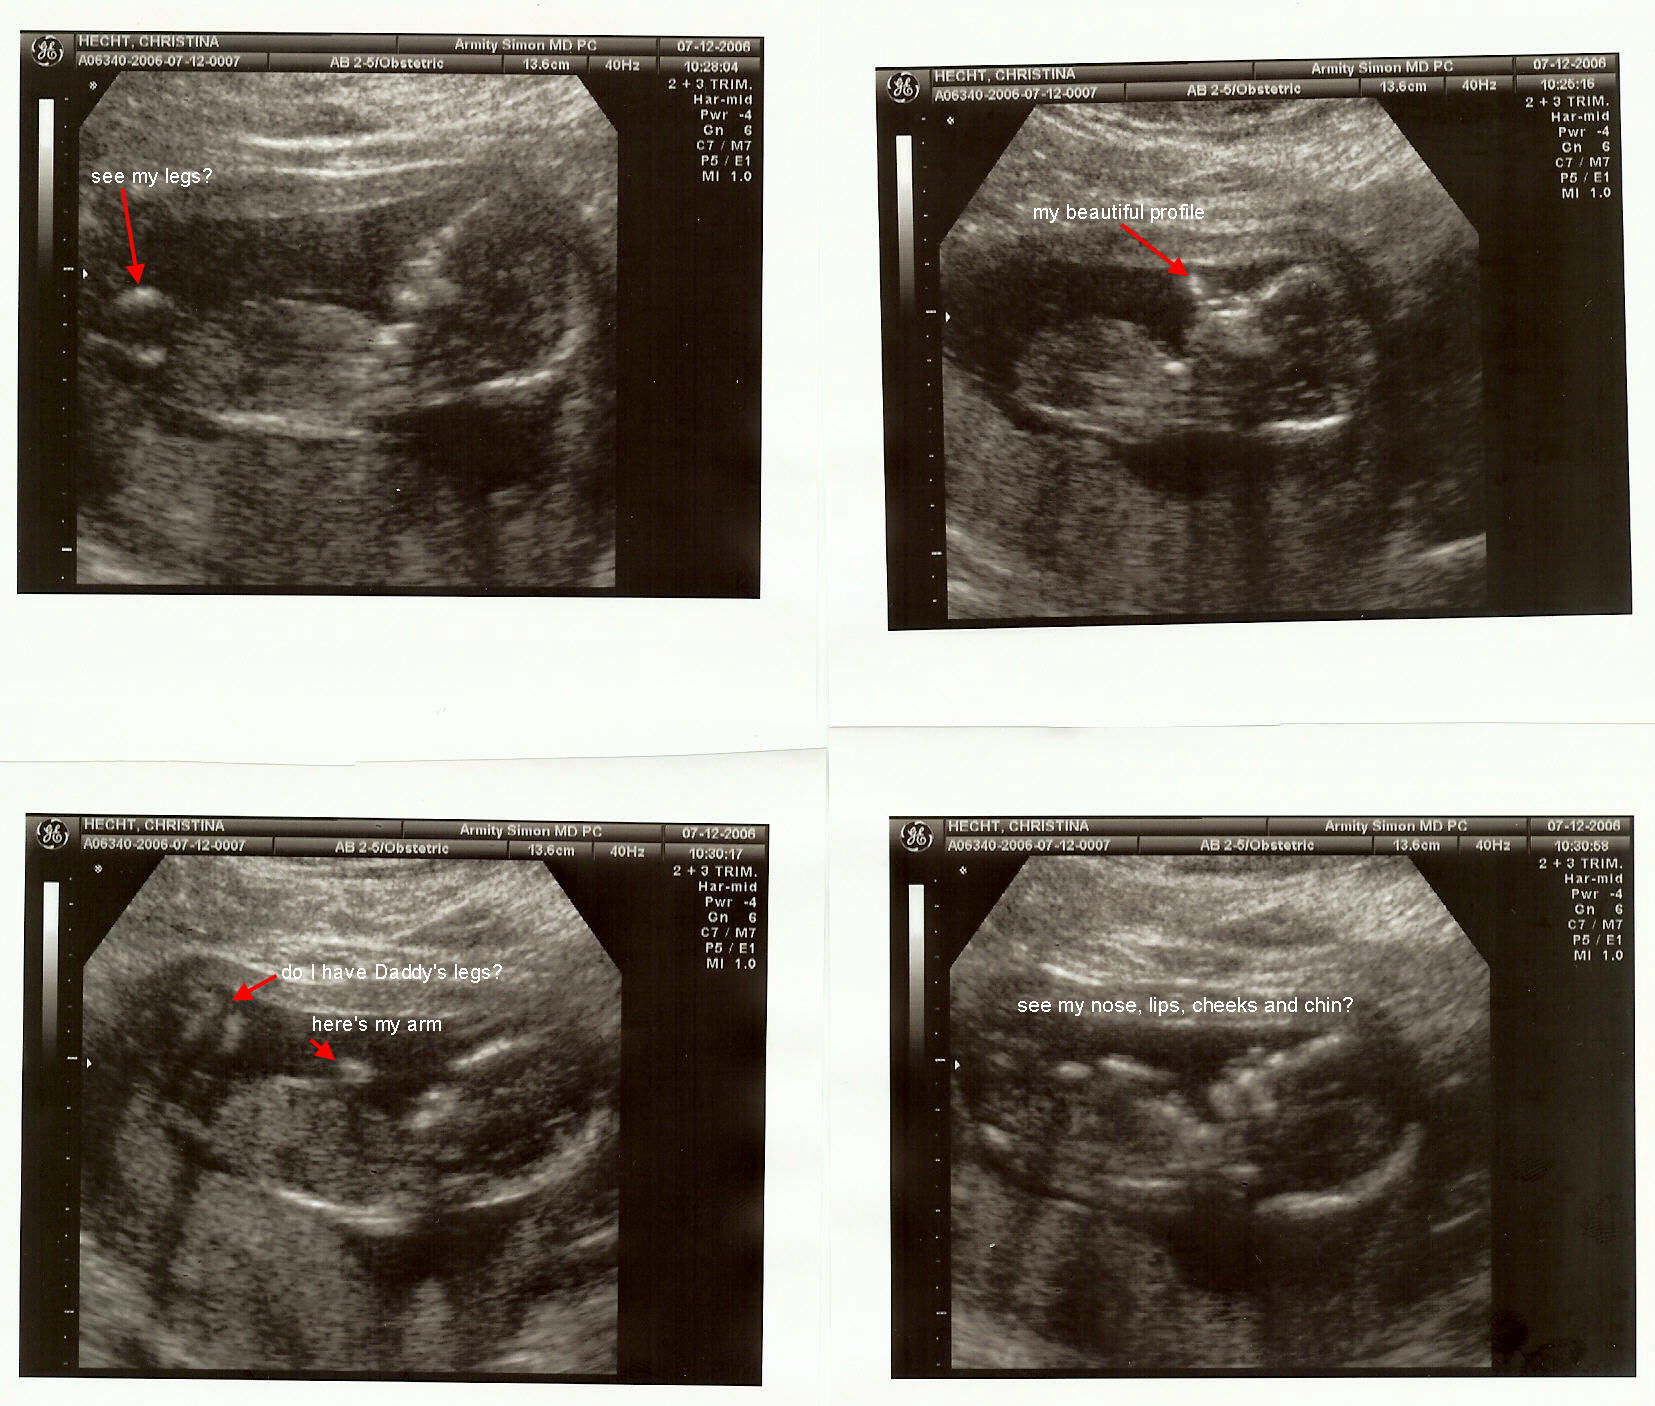

Oh, just got the first picture of "Babe" here tis...

Attached Images

File Type: jpg ultrasound 071206.jpg (313.4 KB, 187 views)

Thanks for the pics Rocky. My daughter has one of those but it is so early in the pregnancy that it does not look like anything yet. Will post them as I get them.